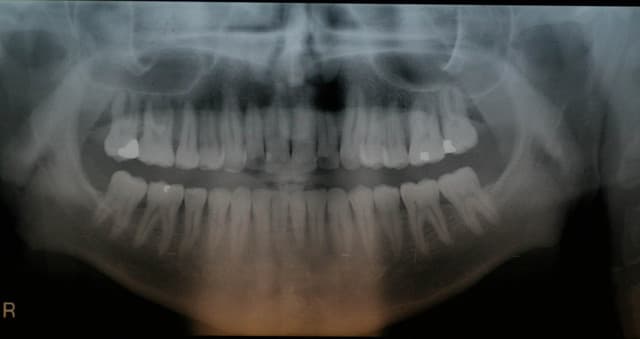

c'est un cas d'ortho chirurgicale du type Lefort1

en bas je sais pas trop mais aucune dent n'est dans son axe, ce qui peut expliquer aussi les recessions gingivale

Des nouvelles fraiches: on va faire de l'ortho d'abord, dentosophie, et pour les recessions on verra après.

Sinon je suis etonné par le niveau osseux.

A votre avis en regard de l'apex de la 22, artefact?